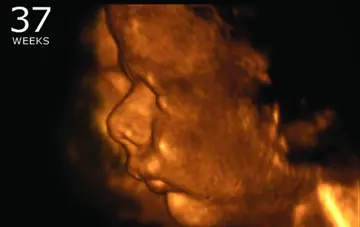

زایمان زودرس